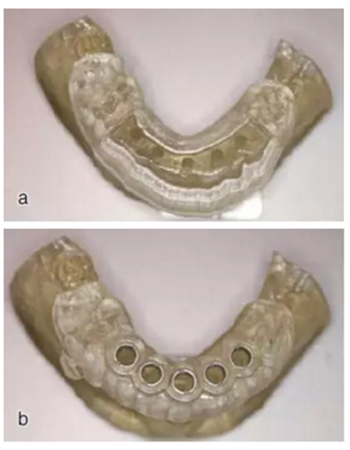

制作導(dǎo)板

根據(jù)種植方案,設(shè)計(jì)并加工出截骨導(dǎo)板和種植導(dǎo)板。圖為截骨導(dǎo)板與種植導(dǎo)板實(shí)物。

圖16 a.截骨導(dǎo)板;b.種植導(dǎo)板